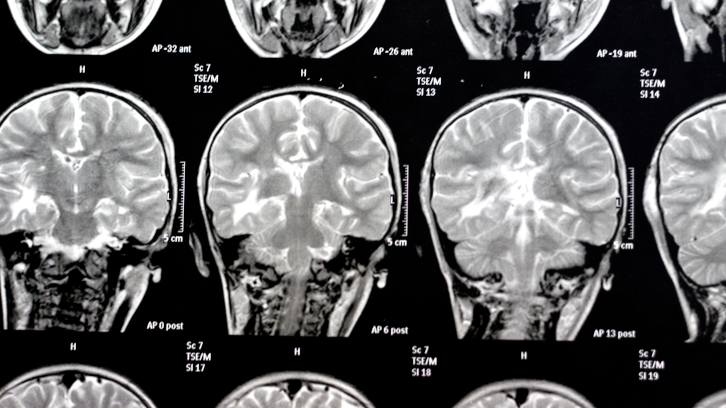

La classificació Taulí-pT1: una nova eina per millorar el diagnòstic del càncer de recte inicial

Un estudi dut a terme per la UAB i l’Hospital Universitari Parc Taulí ha desenvolupat la classificació Taulí-pT1 per ajudar a concretar quina cirurgia convé més...